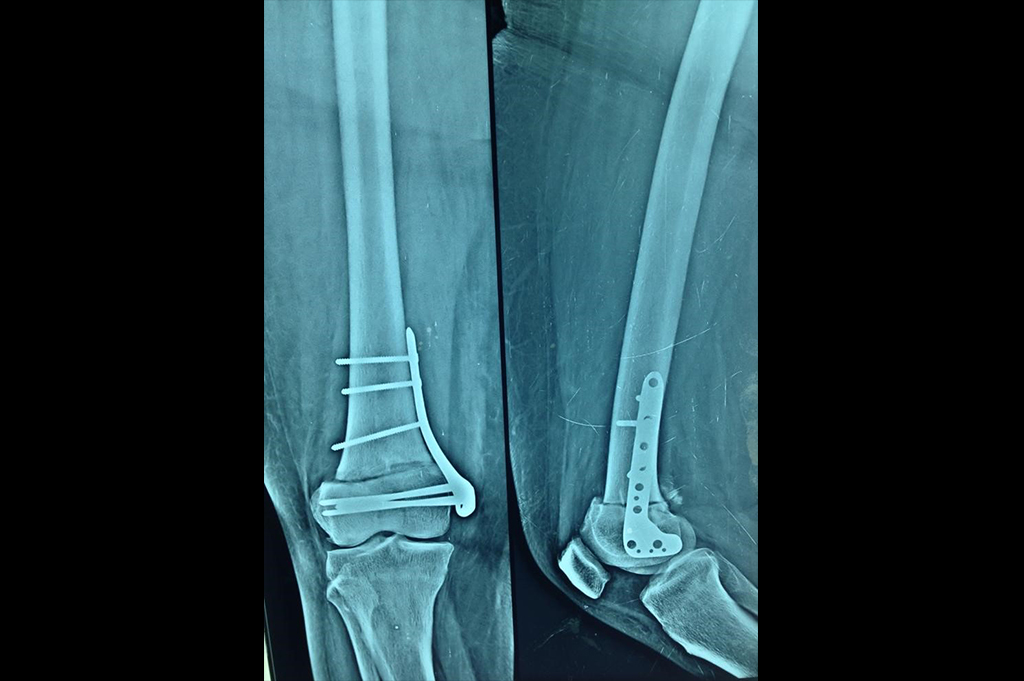

Osteoarthritis – High Tibial Osteotomy - HTO